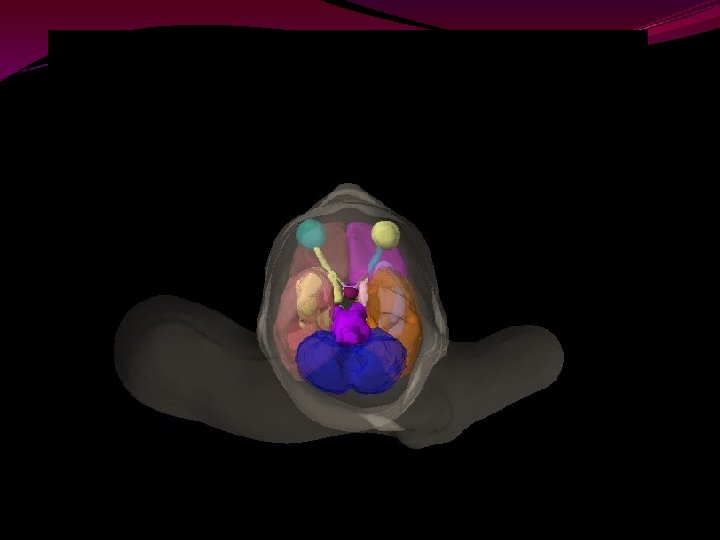

Basal Ganglia

Caudate The round body bulging into the lateral ventricle and forming its floor is the caudate nucleus

Thalamus located near the center of the brain and controls input and output to and from the brain sensation of pain and attention.

borders on the 3 rd ventricle. major importance in both sensory and motor systems. The line of attachment of the roof of this ventricle is marked by a horizontally oriented ridge, the stria medullaris thalami. medial surface of the 2 thalami fuse in many brains called the interthalamic adhesion or massa intermedia. Posteriorly, the thalamus protrudes over the most rostral part of the brainstem. Anteriorly, it abuts the interventricular foramen. No sensory information (except olfactory information) reaches the cerebral cortex without prior processing in the thalami. anatomical loops characteristic of motor systems, typically involve thalami.

Putamen & Globus Pallidus

Insular cortex buried in the depths of the lateral sulcus. It is concealed from view by portions of the frontal, parietal, and temporal lobes. The portion of a given lobe overlying the insula is called an operculum (L. lid). There are frontal, parietal, and temporal opercula.